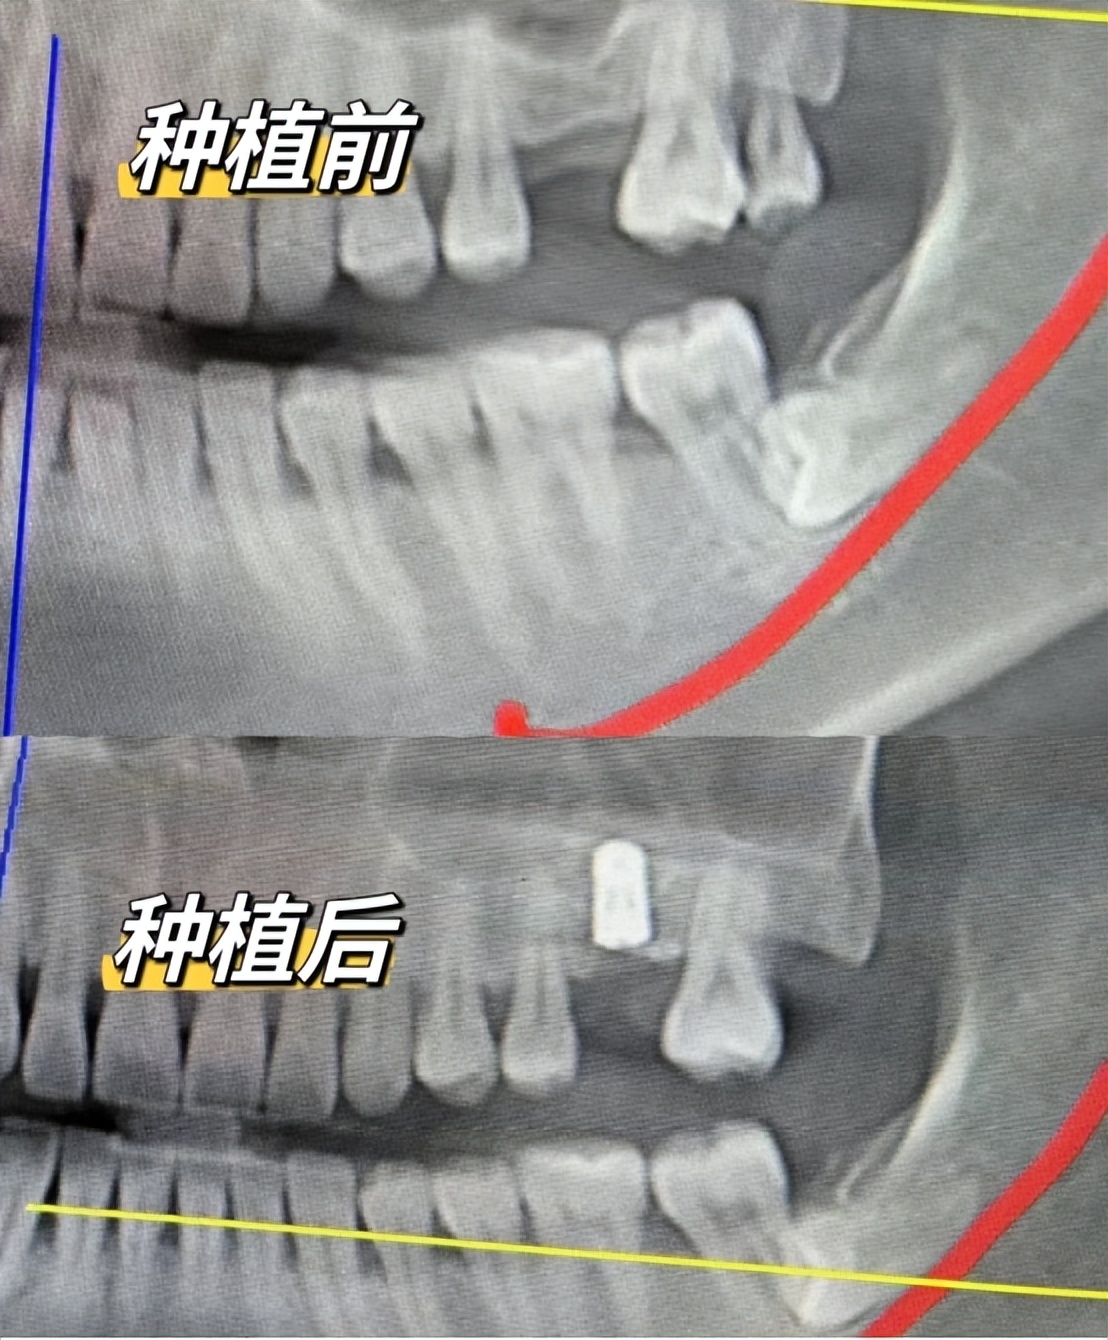

我的牙齿问题属于乳牙滞留,恒牙先天缺失,然后乳牙开始松动了,我就想尽快种植一下,当时一共种了两颗牙,从取模、戴临时牙到正式牙安装上大概3个多月,开始正常使用至今使用已经接近4年了!